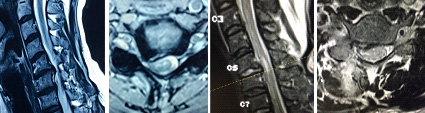

| Gambar 4. Sebelum PSCD dan Sesudah PSCD, Pasien usia 41 tahun. |